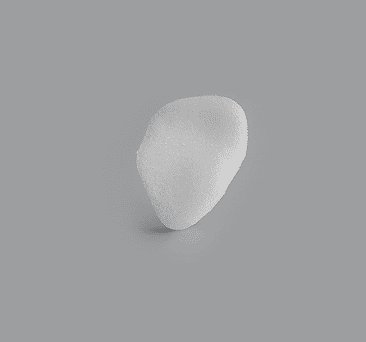

Conical Orbial Implant

Enophtalmos Wedge